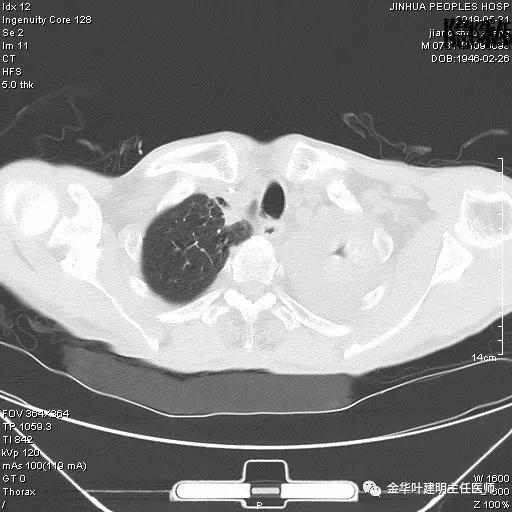

考虑左侧大量胸腔积液,遂进一步胸部CT检查:

以上是肺窗表现,下面为纵隔窗影像: